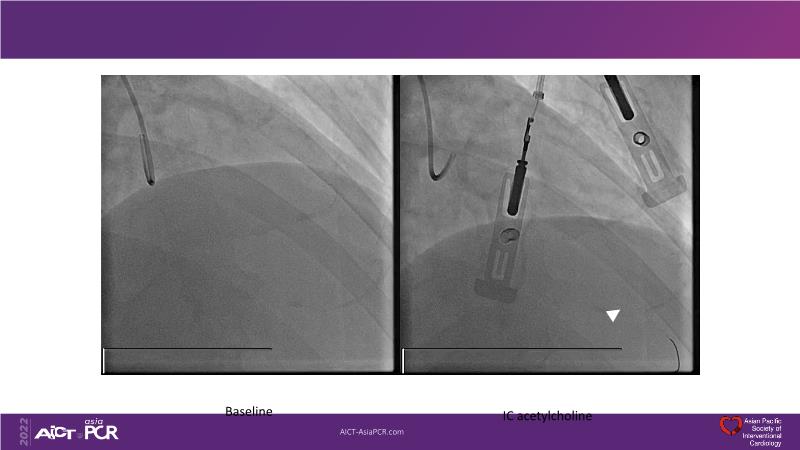

- To understand the role, prevalance and diagnosis of microvascular dysfunction in patients with ischaemia and normal coronary arteries (INOCA)